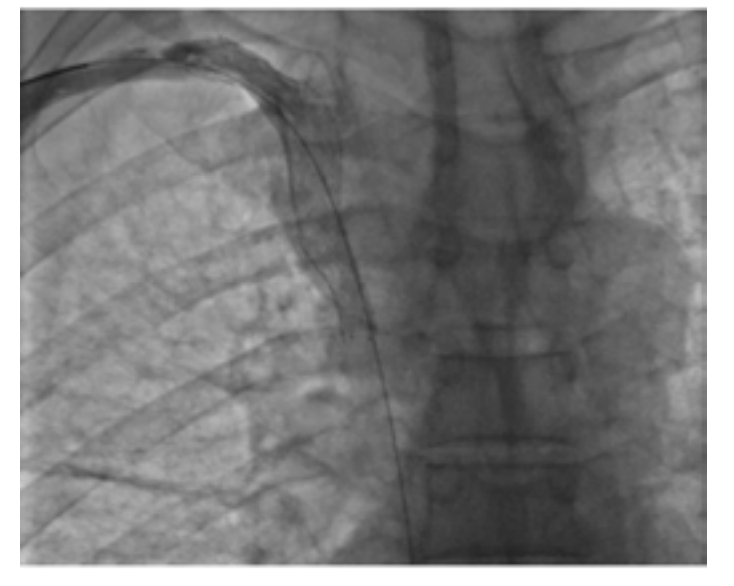

From a therapeutic point of view, endovascular treatment of SVCS had been performed under local anesthesia. Percutaneous vena femoral approach was carried out in 2 cases. Three patients also required the use of the basilica pathway. Before stenting, the caval stenosis was dilated two or three times for almost 10 minutes by means of balloon inflation to the estimated diameter in three cases. We also routinely performed post-stent dilatation. In all procedures, a self-expanding stent had been deployed. The details regarding the stent deployed are summarized in Table 1. As an immediate follow-up, the patients experienced a quick relief of symptoms between 48-72 hours.

Despite technical diversity implemented, we believe that SVCS endovascular treatment should be performed, according to the recommendations of the French Society of CardioVascular Imaging (SFICV).20 In fact, it had to be carried out, firstly, with an undersized caliber balloon, 2 mm smaller than the diameter of the SVC measured. After the deployment of self-expanding stents, inflation should be carried out at low pressure. Many reasons are behind this logic. Firstly, the stent complete expansion will occur spontaneously in the hours or days that follow the procedure, it will avoid hemorrhagic complications due to dissection of the venous wall, rupture or tamponade. In addition to that, the post-inflation corrects the eccentric character and accelerates the self-expansion of the Wallstent. At last, this technique helps to press the thrombus against the endoprosthesis, preventing emboli migration.